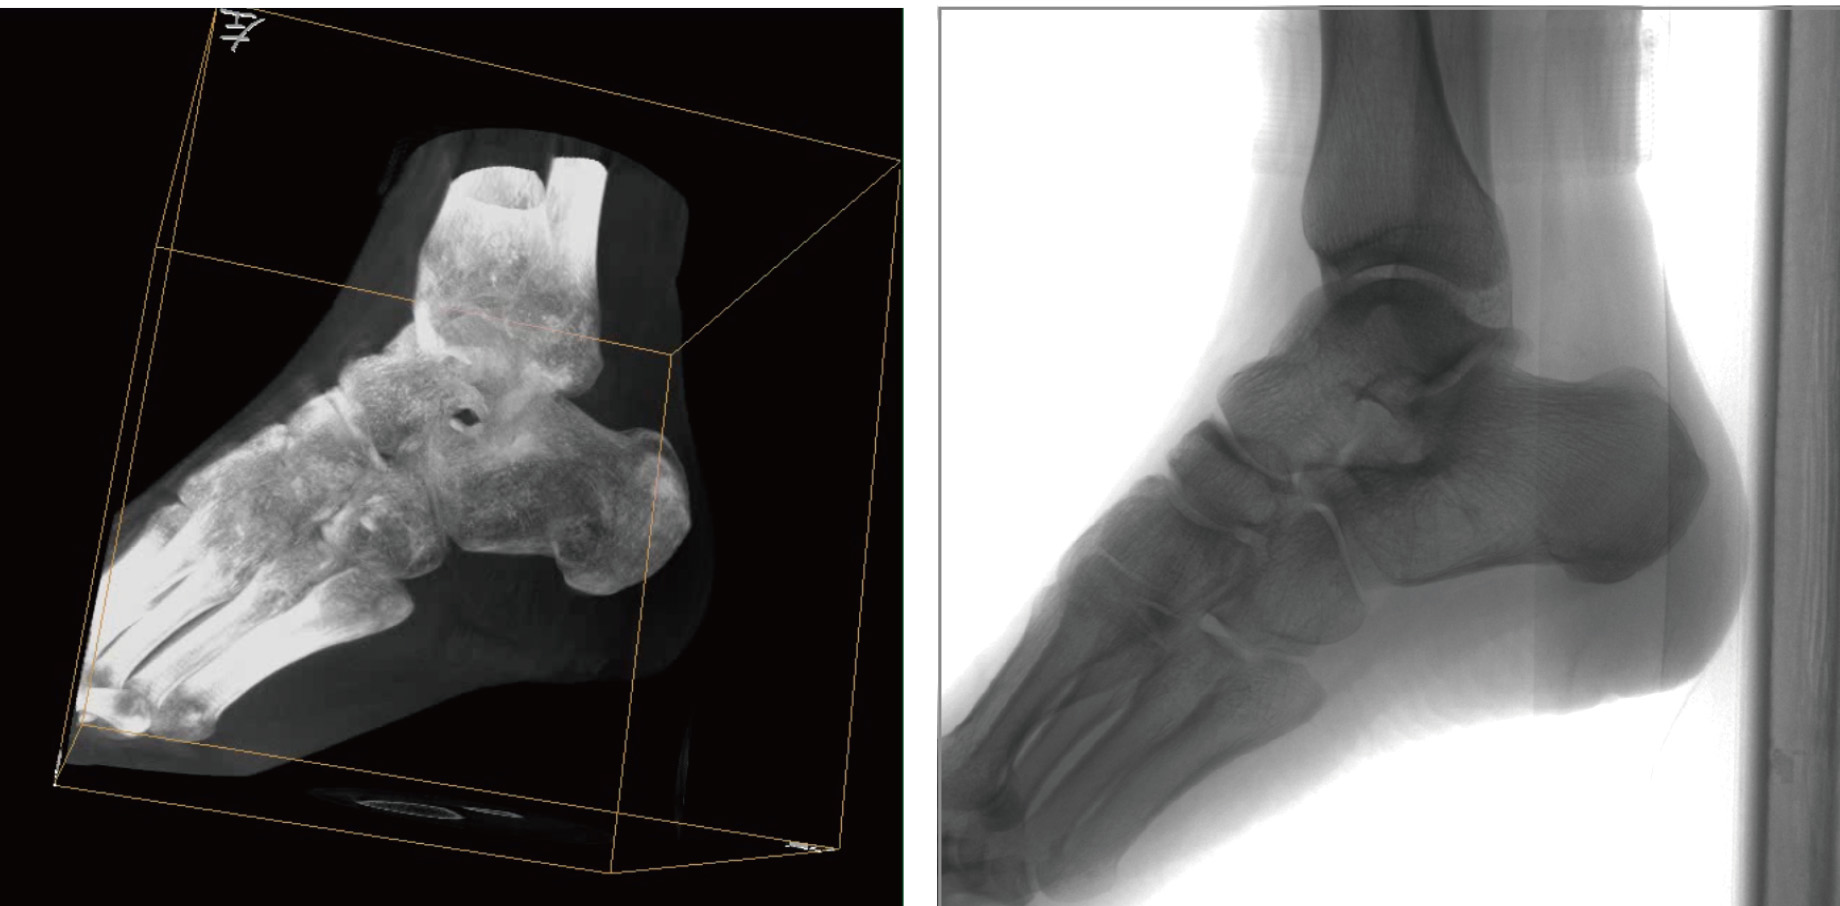

骨科三維C形臂透視導(dǎo)航已在骨科手術(shù)中得到廣泛,極大優(yōu)點(diǎn)就是術(shù)者可以在術(shù)中實(shí)時獲得患者三維重建的圖像,可以根據(jù)二維圖像和三維圖像的對比來實(shí)現(xiàn)手術(shù)的微創(chuàng)和準(zhǔn)確性,且術(shù)者還可以在術(shù)中根據(jù)實(shí)際情況隨時改變手術(shù)治療的方案,而不必過多地?fù)?dān)心定位不準(zhǔn)確帶來的一系列問題。

PLX7500骨科三維C形臂通過采集,能在術(shù)中快速地生成橫斷面、矢狀面、冠狀面和可旋轉(zhuǎn)的立體圖像,給術(shù)者提供360°無死角的觀察角度,準(zhǔn)確判斷骨組織和植入物的情況,為手術(shù)的實(shí)施提供保障,極大提高手術(shù)成功率,減少并發(fā)癥概率。